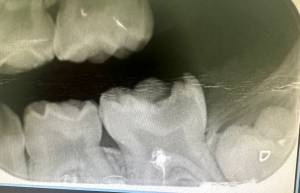

Durante la exploración clínica, realizamos una radiografía inicial que nos permitió confirmar el diagnóstico: el cuerno pulpar del diente afectado se había retraído por completo. Este hallazgo determinó la necesidad de realizar un tratamiento pulpar más profundo: una pulpectomía.